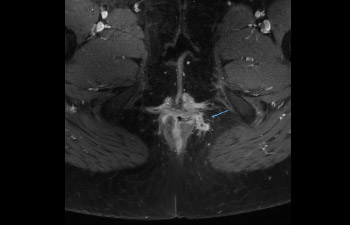

Ingenia Elition fornisce un'eccellente qualità delle immagini ed esegue esami RM a una velocità fino al 50% più elevata¹.

Velocità applicata sempre e correttamente.